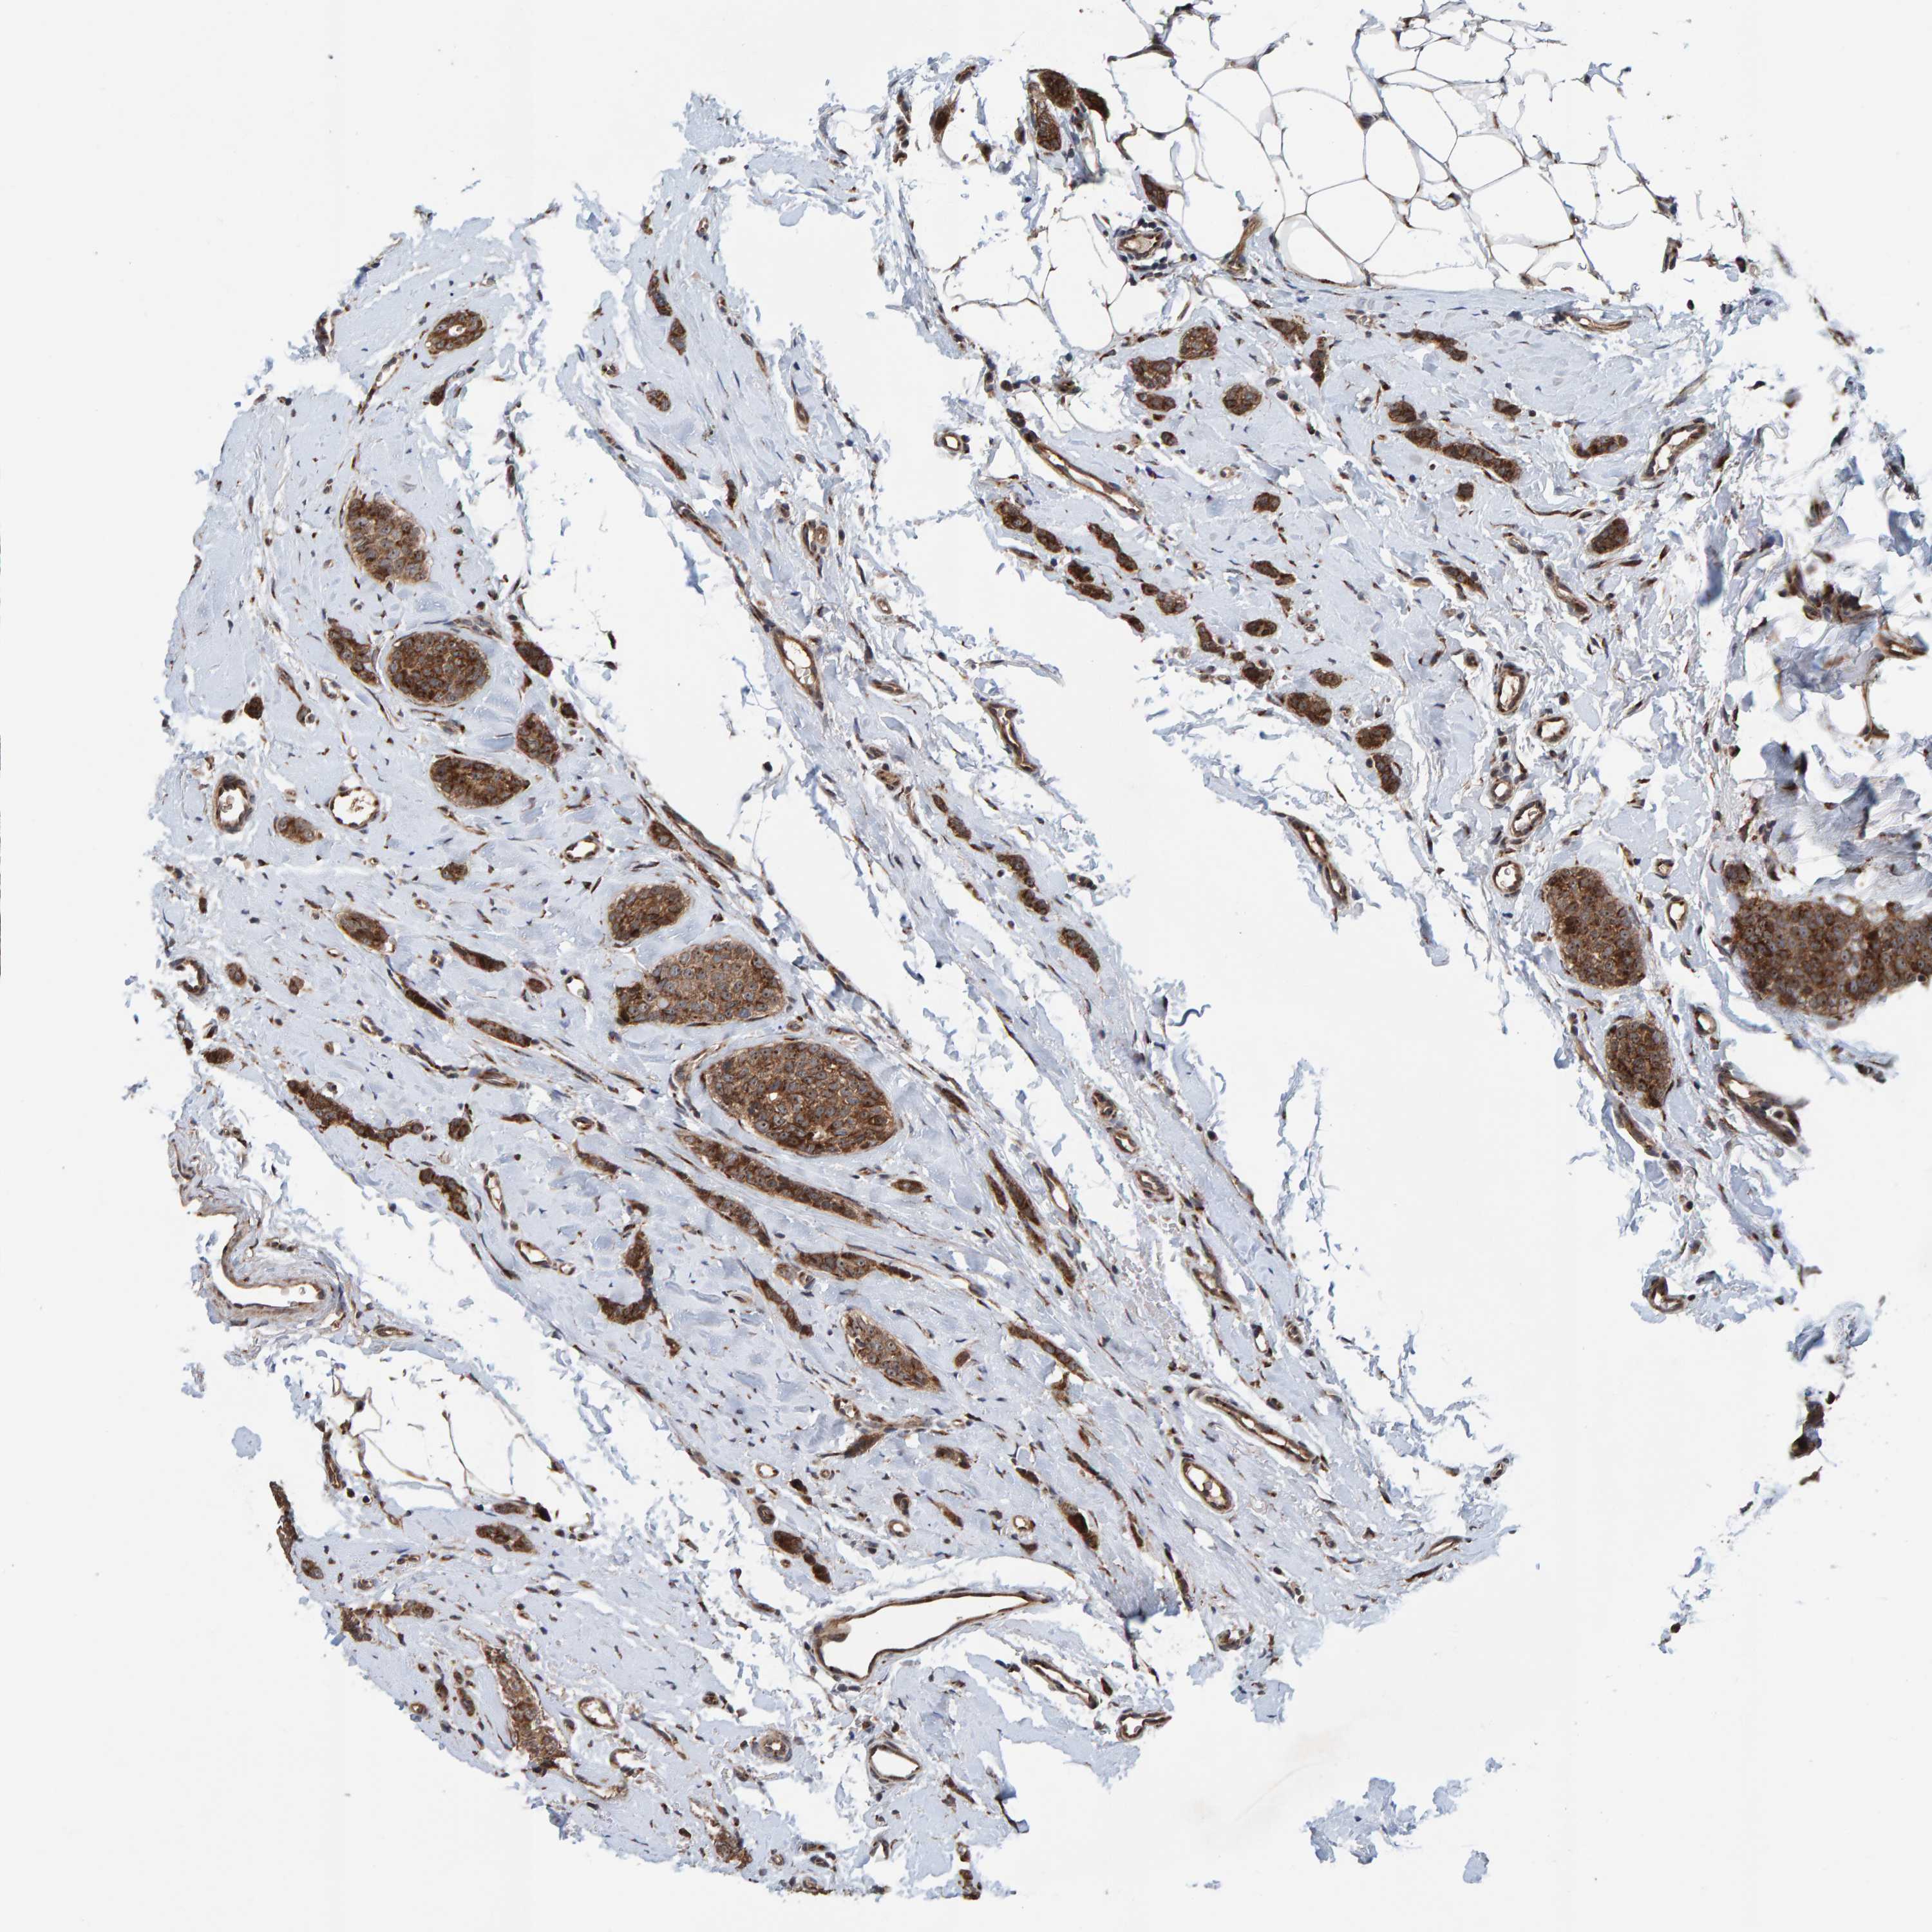

CANCER BREAST CANCER Show tissue menu

BRCA TCGA BRCA VALIDATION PROTEIN EXPRESSION